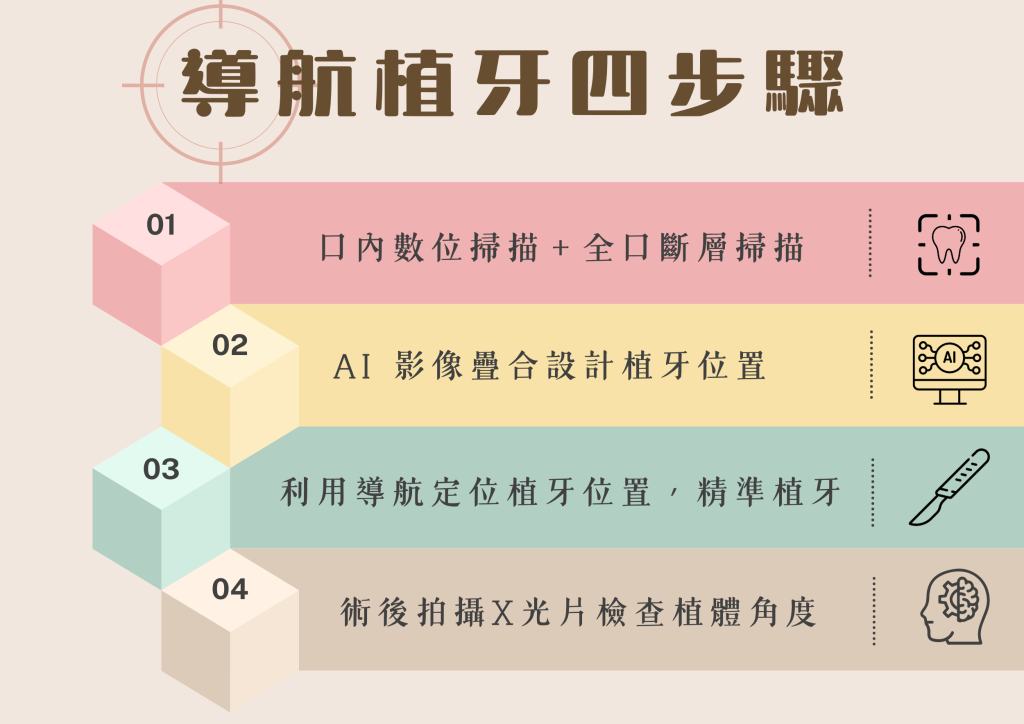

Q3: 導航植牙的步驟流程?

Navident 4D 導航植牙,在手術前必須搜集完整資料,使用醫師必須熟悉導航機器和軟體有足夠熟悉和認知才能達到接近 100% 精準。郭光哲醫師為 Navident 導航原廠合作講師,除了清楚了解機器原理和軟體操作之外,更有 6 年以上的導航使用經驗,有能力提供每個選擇導航植牙的患者更多的保障。